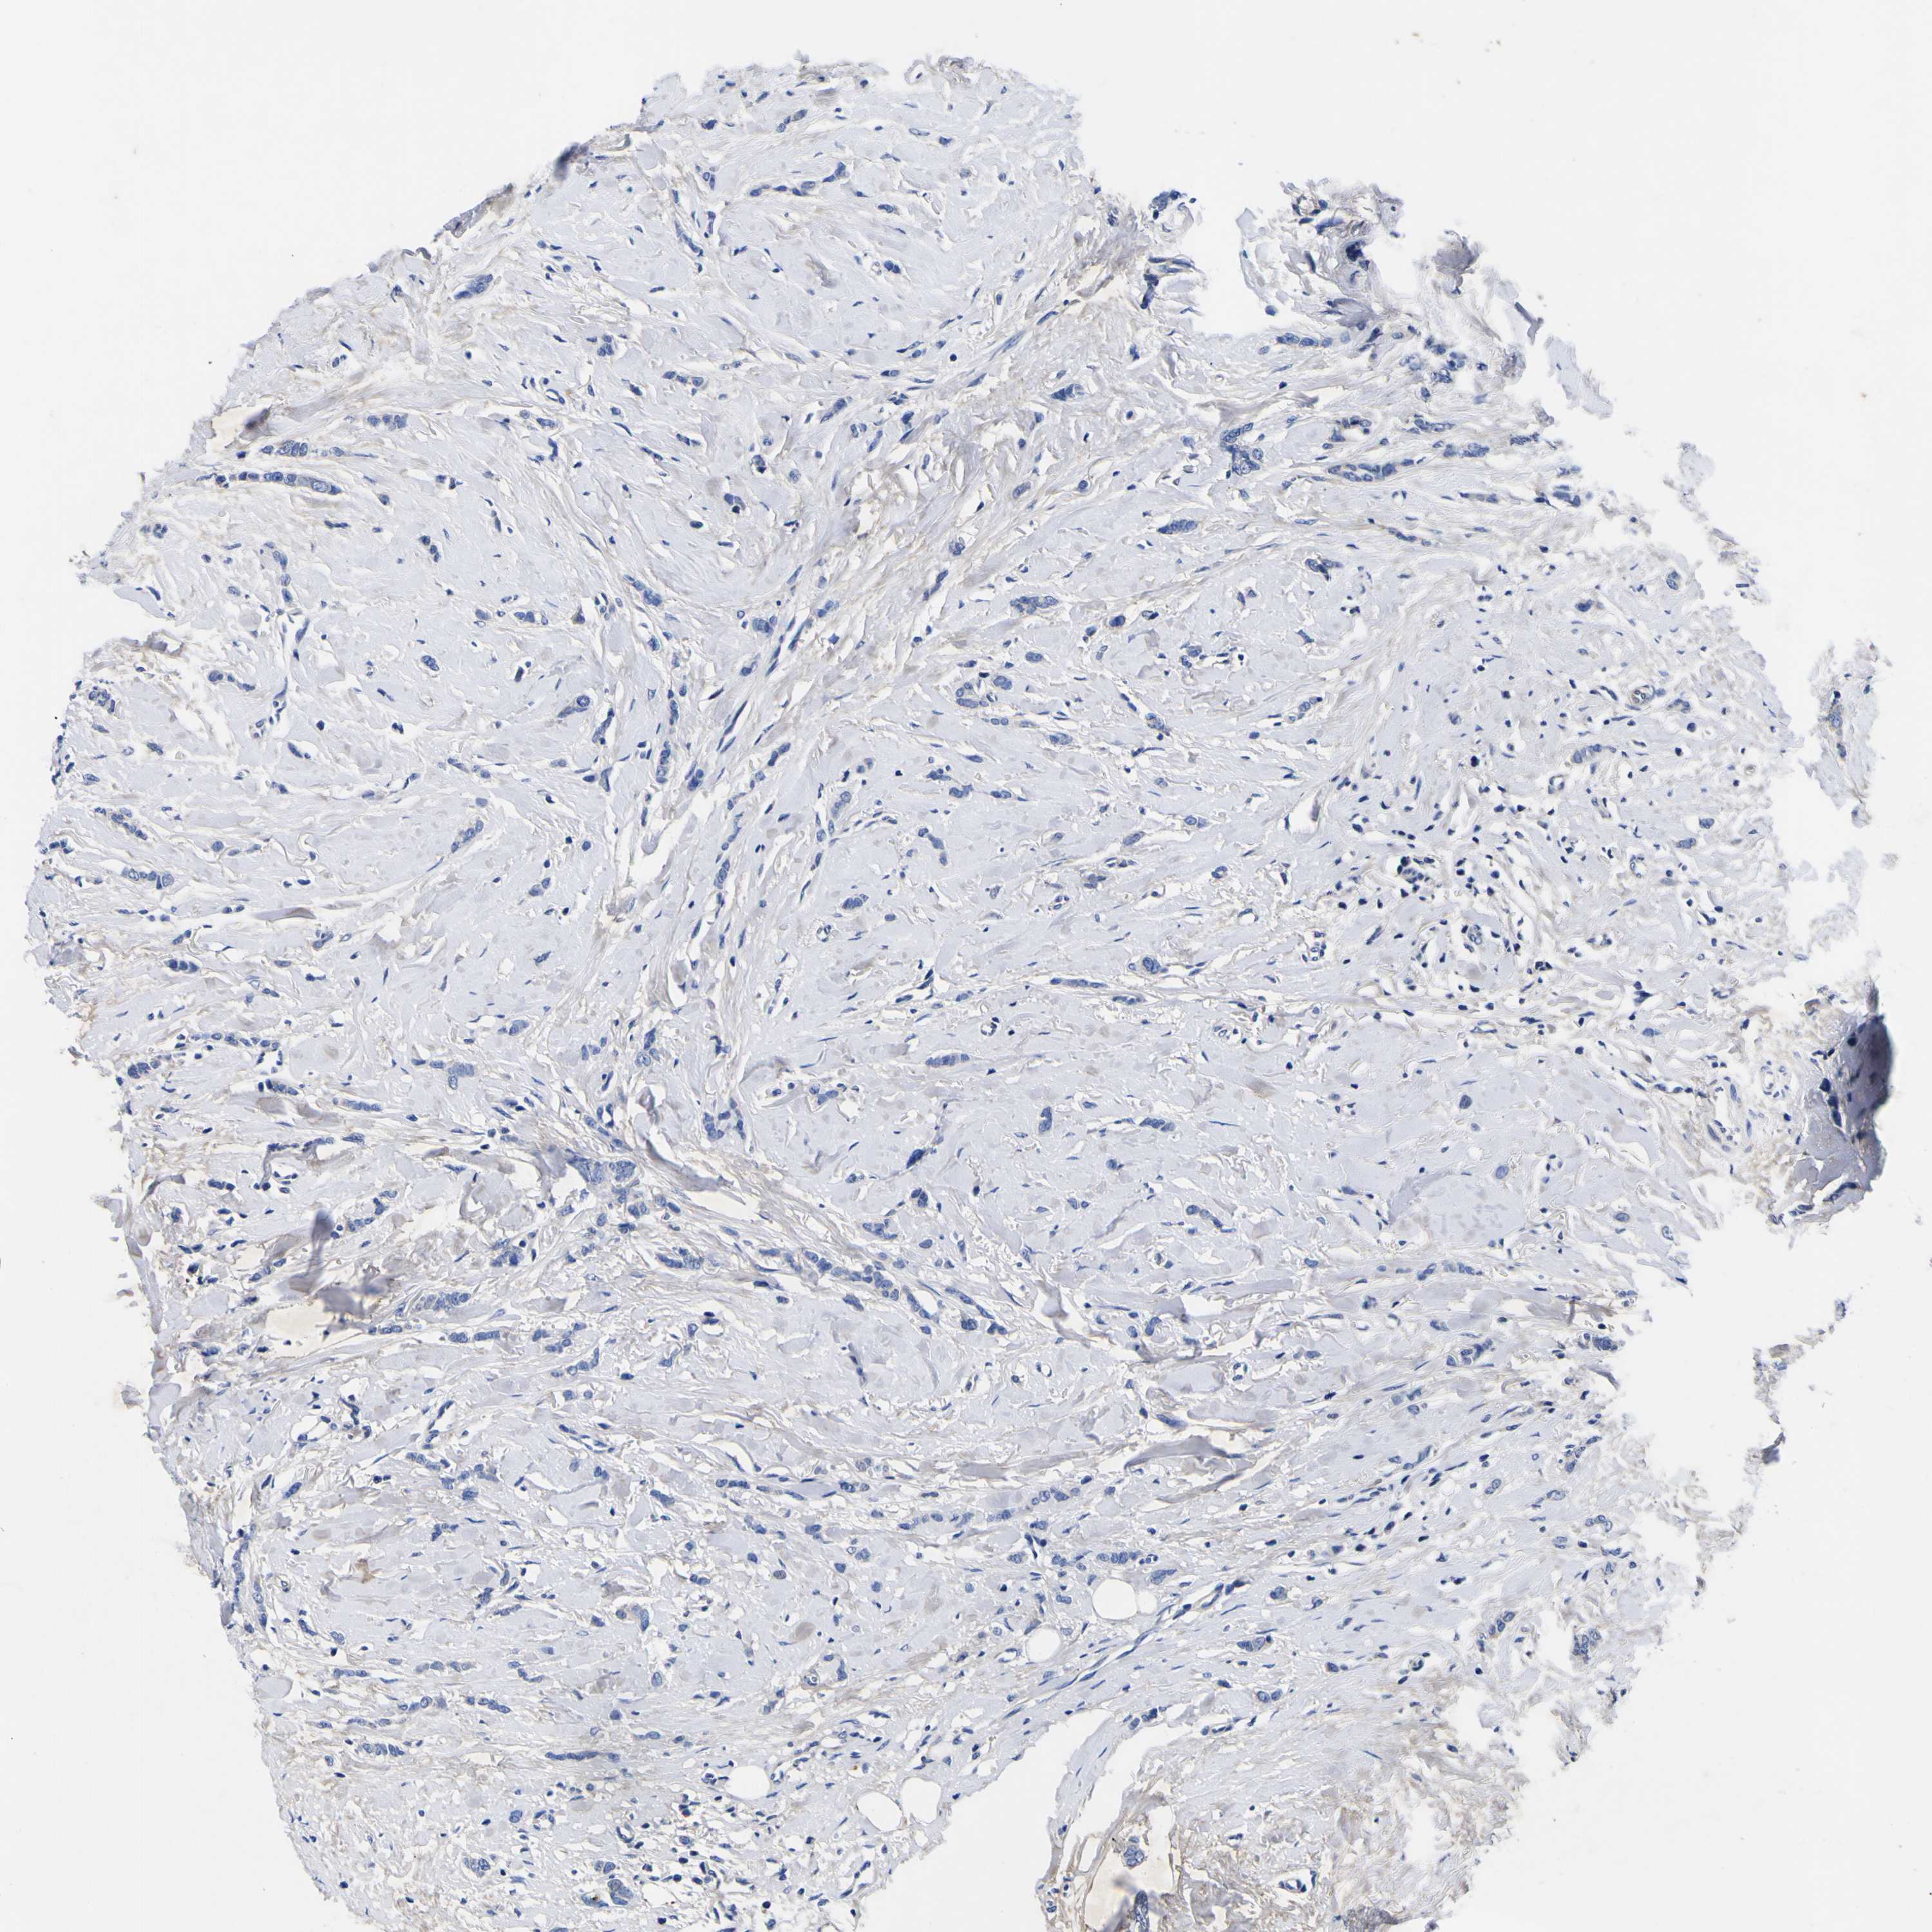

CANCER BREAST CANCER Show tissue menu

BRCA TCGA BRCA VALIDATION PROTEIN EXPRESSION